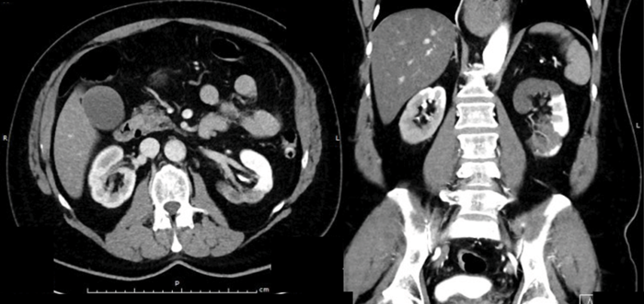

The adrenals

Uropathology: what’s the diagnosis?